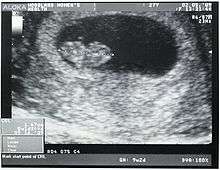

Crown-rump length (CRL) is the measurement of the length of human embryos and fetuses from the top of the head (crown) to the bottom of the buttocks (rump). It is typically determined from ultrasound imagery and can be used to estimate gestational age.

The embryo and fetus float in the amniotic fluid inside the uterus of the mother usually in a curved posture resembling the letter C. The measurement can actually vary slightly if the fetus is temporarily stretching (straightening) its body. The measurement needs to be in the natural state with an unstretched body which is actually C shaped. The measurement of CRL is useful in determining the gestational age (menstrual age starting from the first day of the last menstrual period) and thus the expected date of delivery (EDD). Different babies do grow at different rates and thus the gestational age is an approximation. Recent evidence has indicated that CRL growth (and thus the approximation of gestational age) may be influenced by maternal factors such as age, smoking, and folic acid intake. Early in pregnancy it is accurate within +/- 4 days but later in pregnancy due to different growth rates, the accuracy is less. In that situation, other parameters can be used in addition to CRL. The length of the umbilical cord is approximately equal to the CRL throughout pregnancy.